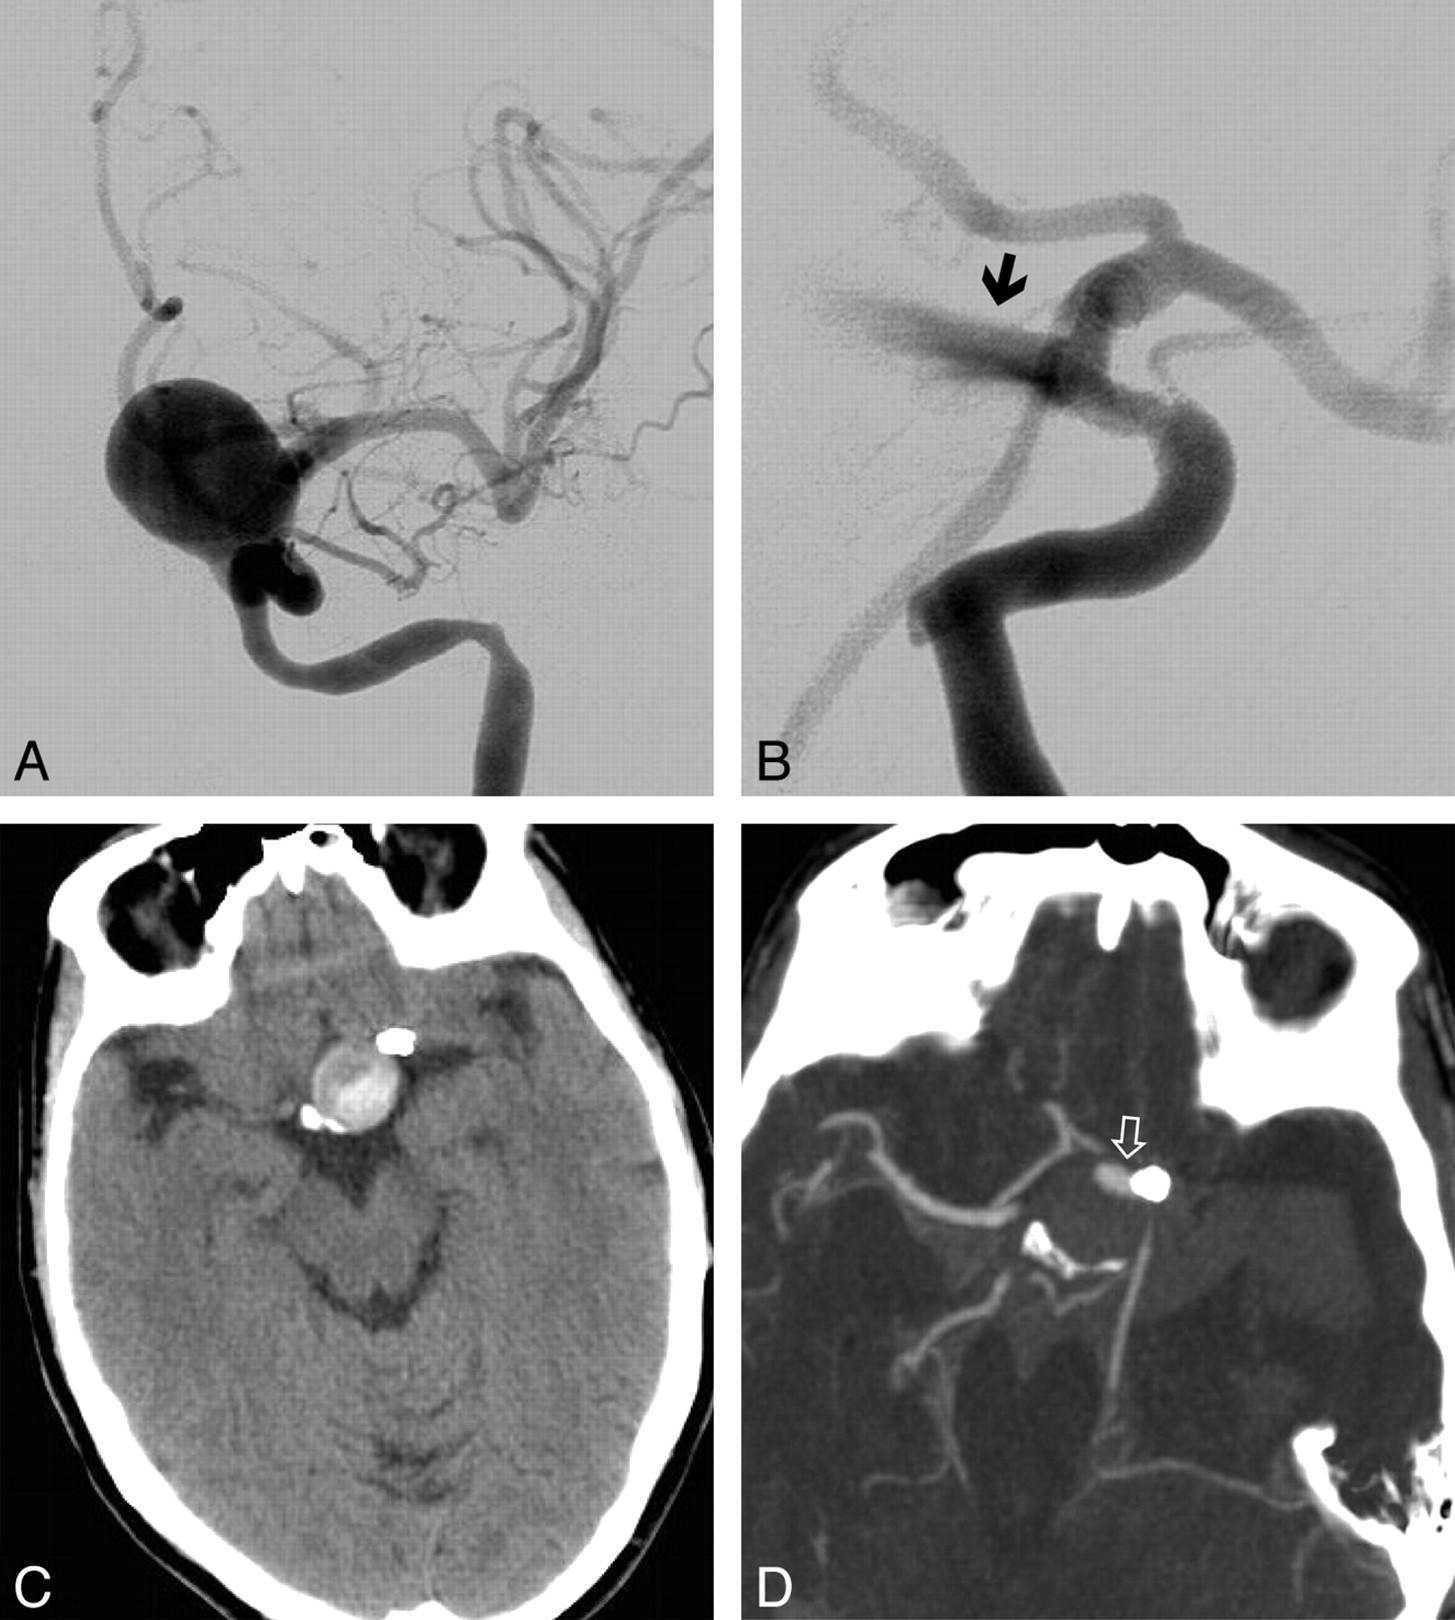

Flow-Pattern Changes after FD Implantation

On the basis of conventional DSA images, an inflow jet was identified before device implantation in 12 of 13 patients. After device implantation, this was still present and clearly identifiable in 11 cases (Fig 1). FD placement increased contrast material stagnation in the aneurysm cavity in all cases.

Patient No. 3. A, Posteroanterior view DSA image of an incidentally discovered left ICA parophthalmic aneurysm. B, Persistence of the inertia-driven inflow jet (arrow) is shown after device deployment. C and D, Nonenhanced CT scan 2 days after intervention shows already partial thrombosis of the aneurysm (C), and a CT angiogram at day 5 shows massive subarachnoid hemorrhage and only a minor portion of the aneurysm that is still perfused, corresponding to the inflow jet area (open arrow) (D).